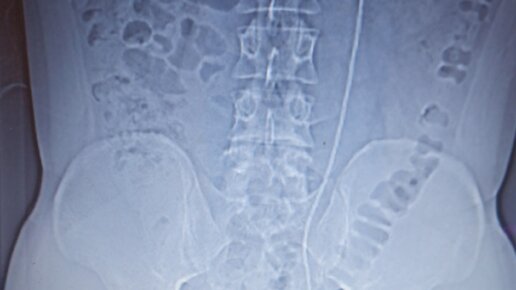

Стент в почке

После удаления и дробления камня, устанавливается стент в почку.